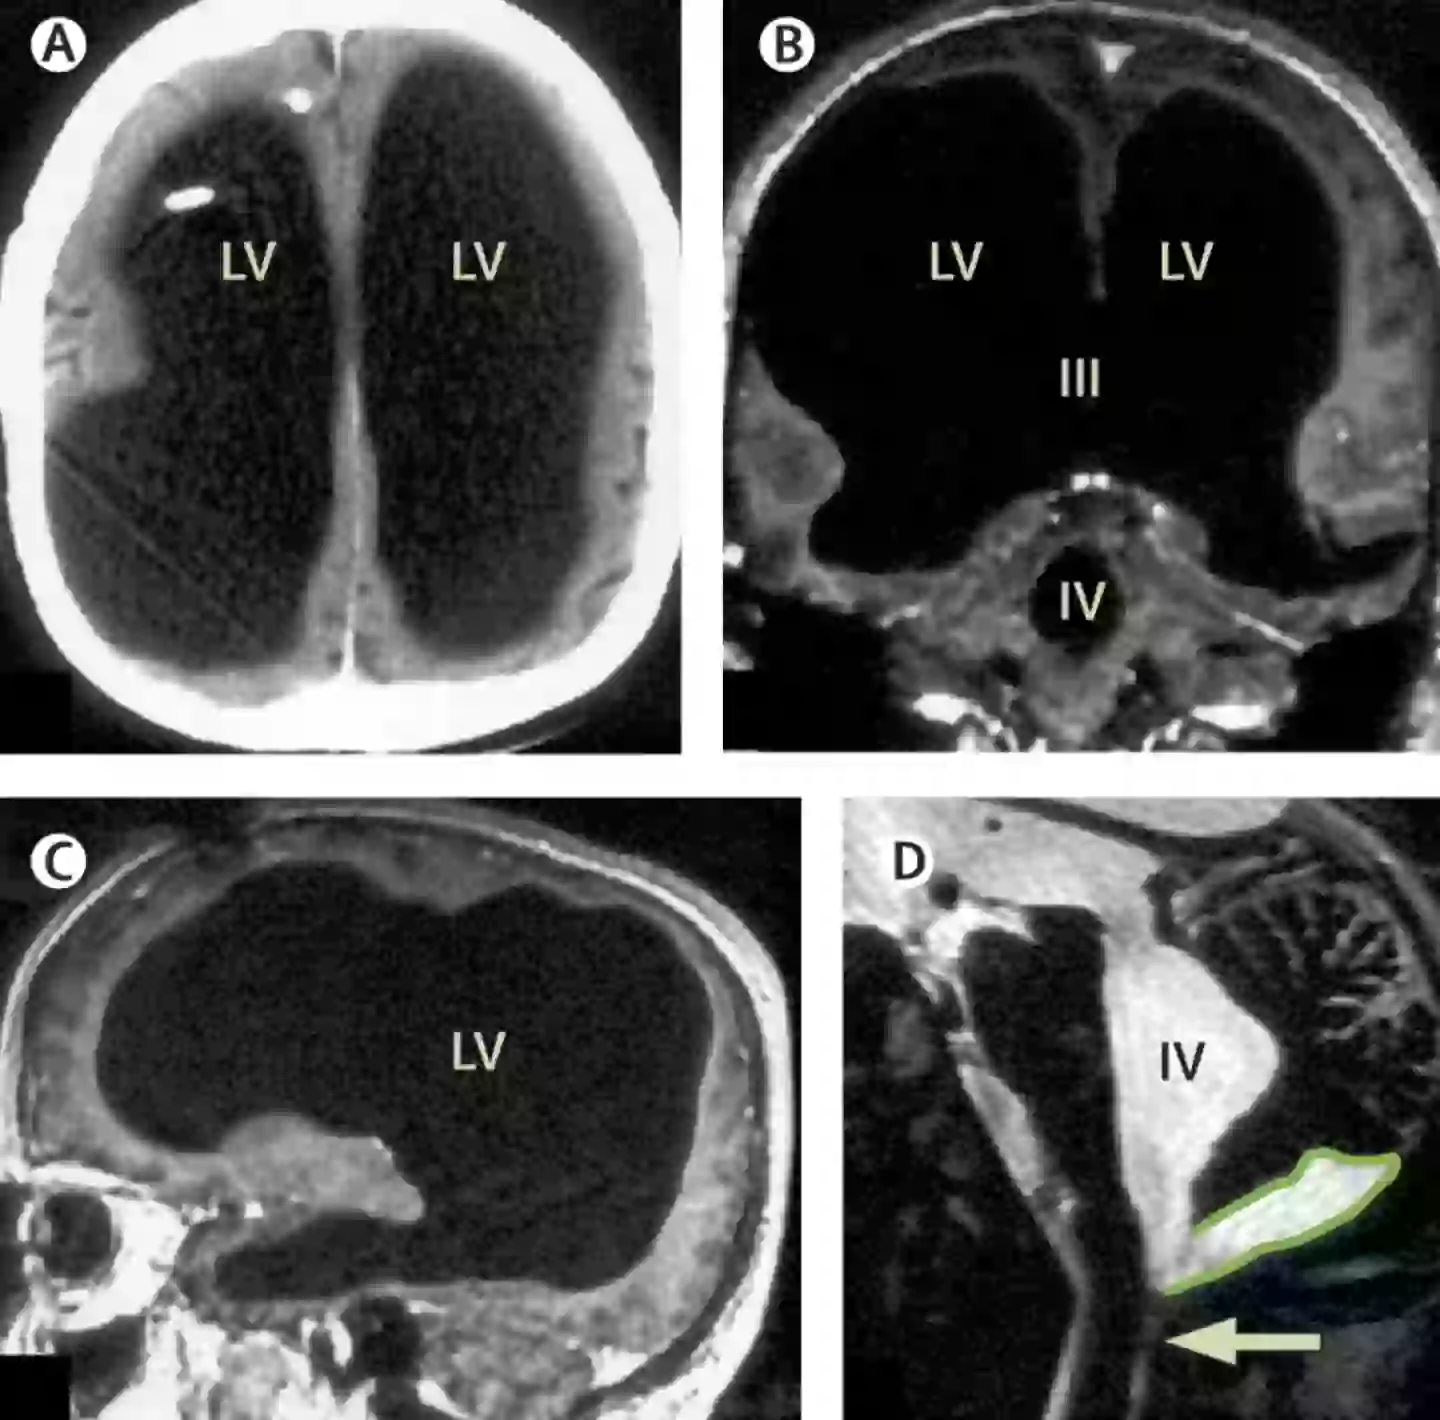

Following an MRI, the scans shown that most of the mans skull was filled with fluid, instead of brain tissue.

While it was initially thought that brain tissue had eroded, scientists now believe that it was compressed by the fluid.

The brain tissue was compressed into a thin outer layer along the edges of his skull, leaving 90 percent of the skill filled with fluid, instead of brain matter.

The condition is the result of hydrocephalus, a disorder involving the build up of fluid in the brain.

The scans left doctors baffled (The Lancet)